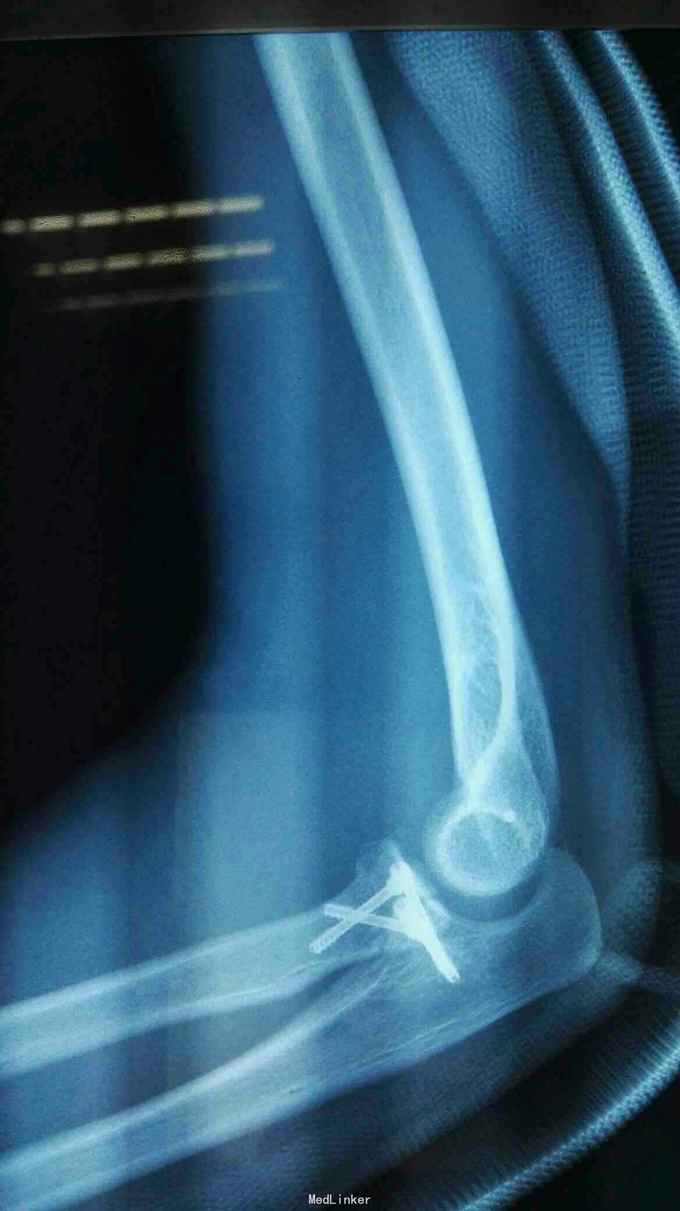

诊断:右肘恐怖三联症。 治疗:伤后第6天在全麻下行右肘恐怖三联症切开复位内固定术,术中先取肘外侧弧形切口,显露桡骨头,用2枚埋头螺钉固定桡骨头,见右肘外侧副韧带尺侧束断裂,用锚钉固定外侧副韧带。取右肘内侧弧形口,显露冠状突,见冠状突骨折块很小,移位较远,复位,2枚螺钉固定,内侧副韧带前束断裂,修补,术后石膏因定。

讨论:恐怖三联症的治疗包括两个方面,骨折的复位固定及内外侧副韧带的修补。木例内外侧副韧带都进行了修补,且术后2周开始锻炼,取得满意的功能康复。。